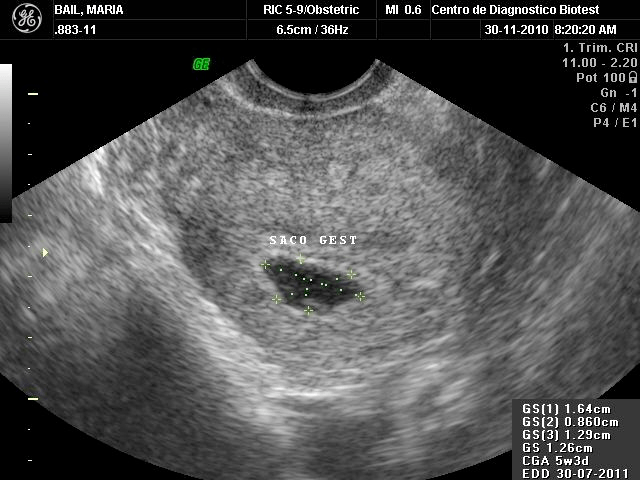

Imagen tomada de: MavCure.com